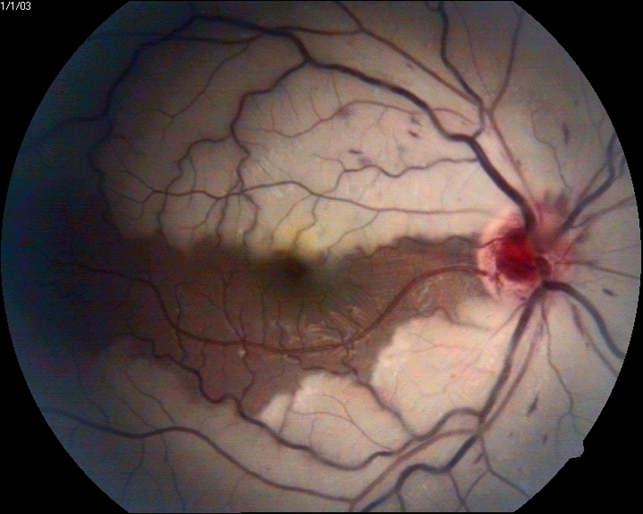

Introduction. Albrecht von Graefes first described central retinal artery occlusion (CRAO) in 1859 as a disastrous ophthalmic emergency characterized by sudden onset, acute painless loss of vision, and a poor prognosis [].All cases of acute CRAO on fundus examination reveal extensive retinal whitening, presence of a cherry red spot, retinal vessel attenuation, and preservation of optic nerve.

Central retinal artery occlusion. Notes (A) Color fundus photograph... Download Scientific